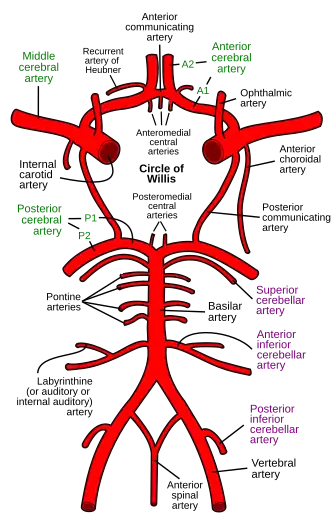

Diagram of the arterial circulation at the base of the brain (inferior view), the circle of Willis is drawn in the upper half. Blood flows up to the brain through the vertebral arteries and through the internal carotid arteries. | |

The circle of Willis (also called Willis' circle, loop of Willis, cerebral arterial circle, and Willis polygon) is a circulatory anastomosis that supplies blood to the brain and surrounding structures in reptiles, birds and mammals, including humans.[1] It is named after Thomas Willis (1621–1675), an English physician.[2]

The circle of Willis is a part of the cerebral circulation and is composed of the following arteries:[3]

- Anterior cerebral artery (left and right) at their A1 segments

- Anterior communicating artery

- Internal carotid artery (left and right) at its distal tip (carotid terminus)

- Posterior cerebral artery (left and right) at their P1 segments

- Posterior communicating artery (left and right)

The middle cerebral arteries, supplying the brain, are also considered part of the Circle of Willis [4]

The left and right internal carotid arteries arise from the left and right common carotid arteries.

The posterior communicating artery is given off as a branch of the internal carotid artery just before it divides into its terminal branches - the anterior and middle cerebral arteries. The anterior cerebral artery forms the anterolateral portion of the circle of Willis, while the middle cerebral artery does not contribute to the circle.

The right and left posterior cerebral arteries arise from the basilar artery, which is formed by the left and right vertebral arteries. The vertebral arteries arise from the subclavian arteries.

The anterior communicating artery connects the two anterior cerebral arteries and could be said to arise from either the left or right side.

All arteries involved give off cortical and central branches. The central branches supply the interior of the circle of Willis, more specifically, the Interpeduncular fossa. The cortical branches are named for the area they supply and do not directly affect the circle of Willis.